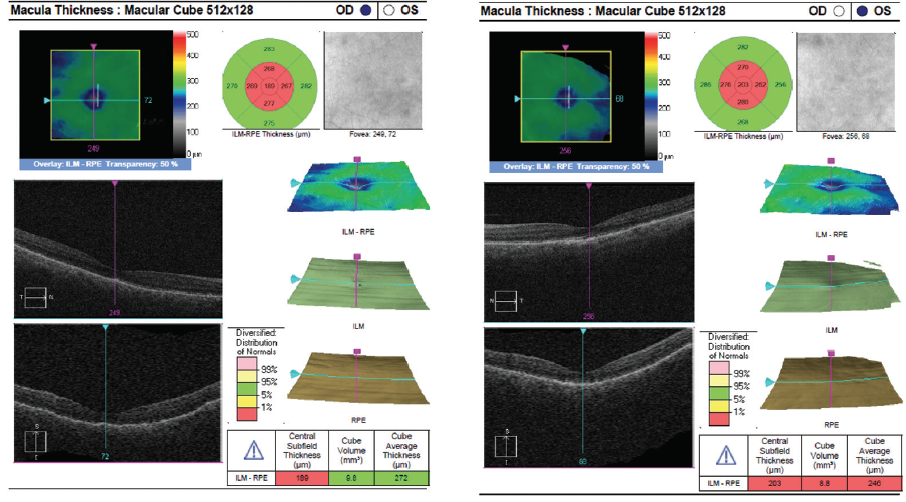

Dilated fundus examination revealed clear media without inflammation OU and numerous deep, discrete, and patchy yellow lesions throughout the posterior pole with irregular borders and multiple areas of distinct retinal elevation OU (Figure 1). The optic nerves were noted to be hyperemic OU without significant elevation, hemorrhage, or obscuration of vessels. Of note, there was no evidence of peripheral pathology or retinal vasculitis. OCT imaging showed numerous areas of intraretinal and subretinal fluid pockets of varying size with notable retinal and choroidal undulation through the macula (Figure 2). Fluorescein angiography showed multiple irregular patchy and pinpoint areas of hyperfluorescent foci throughout the posterior pole with leakage and distinct pockets of pooling in the later frames (Figure 3).

Figure 2. OCT shows multiple pockets of intraretinal and subretinal fluid with undulation of the retina and choroid OU on initial presentation.

Figure 5. OCT shows decreased intraretinal and subretinal fluid after initiation of therapy.

The patient showed a robust initial response to steroids with significant improvement in her vision and anatomy. Within 1 week, her VA had improved to 20/100 OD and 20/70 OS. Fundus examination showed improvement with less defined lesions (Figure 4), and OCT showed significant reduction in fluid (Figure 5). After 1 month of treatment, her vision had improved to 20/50 OD and 20/40 OS, with further improvement seen on fundus findings (Figure 6) and near complete resolution of fluid on OCT (Figure 7). Continued improvement was seen 6 weeks after steroid therapy was initiated (Figure 8 and Figure 9). The marked improvement in structure and function with oral prednisone treatment, without ATT treatment, led to a presumed diagnosis of VKH disease.

Figure 7. OCT at 4 weeks of oral prednisone steroids show near resolution of retinal fluid OU.

Figure 9. OCT at 6 weeks of oral prednisone show complete resolution of retinal fluid OU.